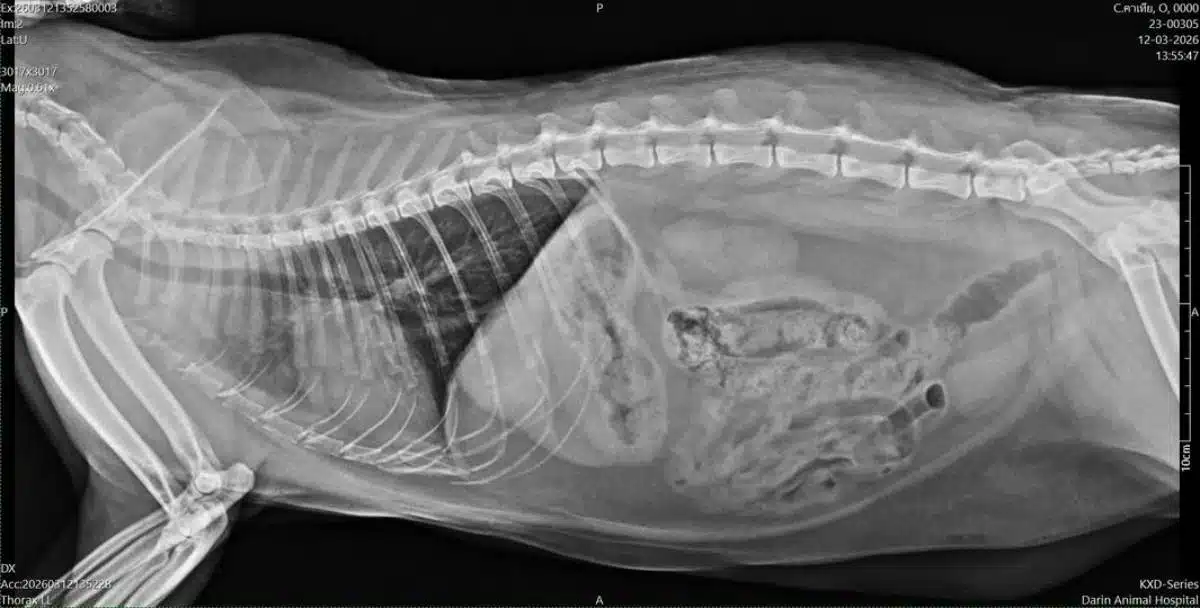

เหตุการณ์นี้ถูกเปิดเผยเมื่อเจ้าของพาแมวไปตรวจสุขภาพประจำปีตามปกติ แต่ผลจากการเอ็กซ์เรย์กลับปรากฏภาพที่น่าตกใจ เนื่องจากพบฝ้าขาวกระจายตัวอยู่บริเวณปอดด้านซ้ายใต้กระดูกอย่างชัดเจน ซึ่งบ่งบอกถึงสภาวะปอดอักเสบที่สะสมมานาน แม้ว่าภายนอกแมวจะมีรูปร่างสมบูรณ์ มีเนื้อมีหนัง และดูมีความสุขดี แต่ภัยเงียบนี้กลับซ่อนตัวอยู่ภายในอย่างแนบเนียน